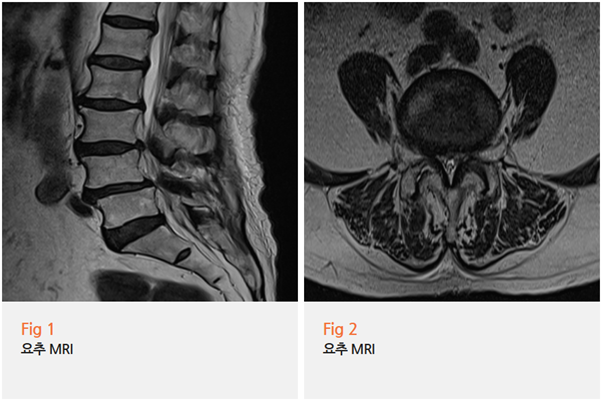

당일 바로 요추 MRI를 찍어보니

예상대로 요추 3-4번, 4-5번 부위에 심한 전방전위증이 보였습니다.

쉽게 말해 허리뼈가 앞으로 밀려나오면서 신경을 심하게 누르고 있는 상태였죠.